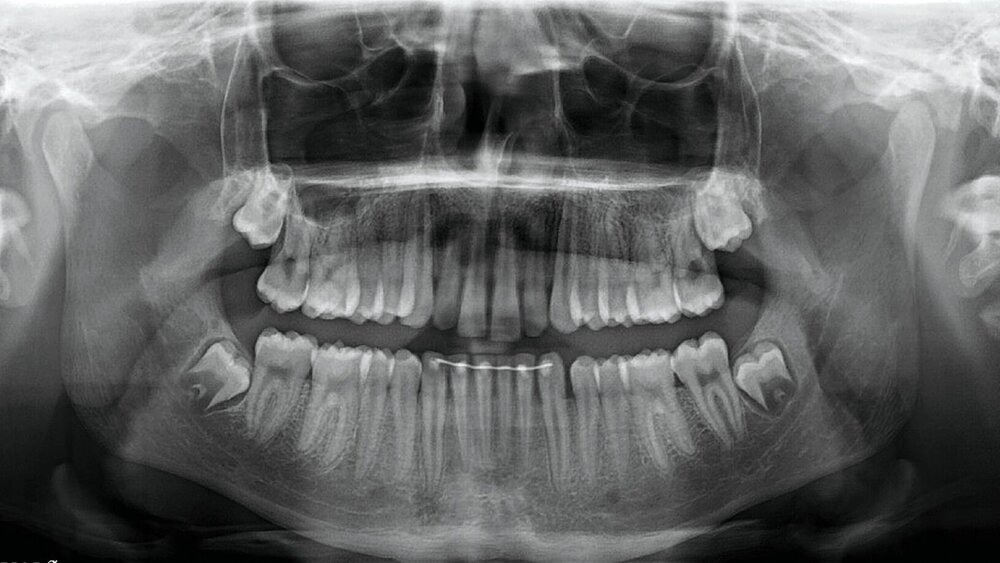

Im Januar 2023 stellte sich ein 17-jähriger Patient nach Überweisung vom Hauszahnarzt mit der Bitte um Mitbeurteilung in der Poliklinik der MKG-Chirurgie der Universitätsmedizin Mainz vor. Im Dezember 2022 waren ihm alio loco die Zähne 18 und 48 in Lokalanästhesie entfernt worden (Abbildung 1). Einige Stunden vor dem Zahnarztbesuch hatte der Patient ein lautes Knacken beim Kauen vernommen, was zu anschließenden Schmerzen geführt habe. Beim Zahnarzt erfolgte daraufhin eine Panoramaschichtaufnahme, die jedoch keinen sicheren Frakturausschluss ermöglichte.